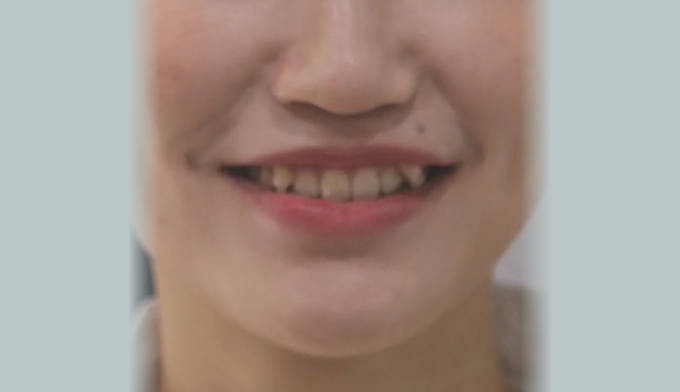

덧니,

덧니,

댜른치과에서 투명교정(인비절라인)치료를 받던 중 치료가 잘 진행되지 않고, 교정기간이 무기한으로 길어진다고 하였습니다.

투명교정은 정확한 치료계획 수립이 필요하며, 치료 중간중간 발생하는 변수를 담당 주치의가 잘 조절해야 문제없이 치료가 진행될 수 있습니다.

덧니가 배열될 수 있는 공간을 먼저 만들기 위해 어금니들을 뒤로 먼저 보내고 미니스크류를 추가적으로 식립하여 보다 더 효과적인 치아이동이 가능하게 만들었습니다.

총 치료기간은 13개월입니다.